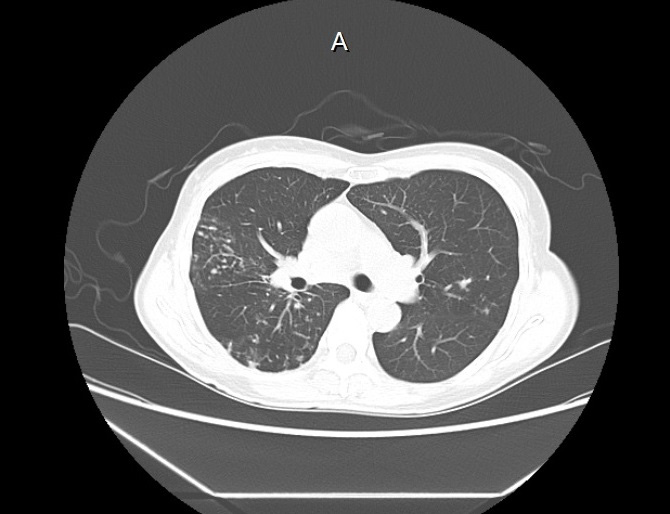

비결핵항산균에 감염된 폐사진